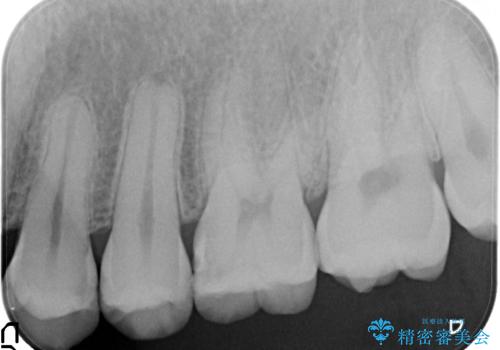

- 虫歯の治療を希望されて来院された患者様です。

歯と歯の間の虫歯が多く、同じブロックの歯をまとめて治療していくこととしました。

今回、幸いにもそんなに大きな虫歯がなかったため、虫歯をとって、セラミックインレーにて修復することが来ました。